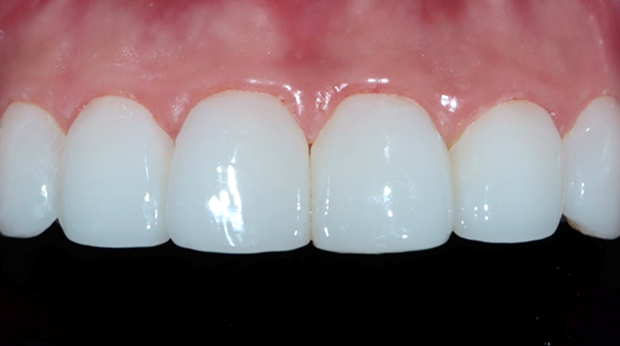

라미네이트